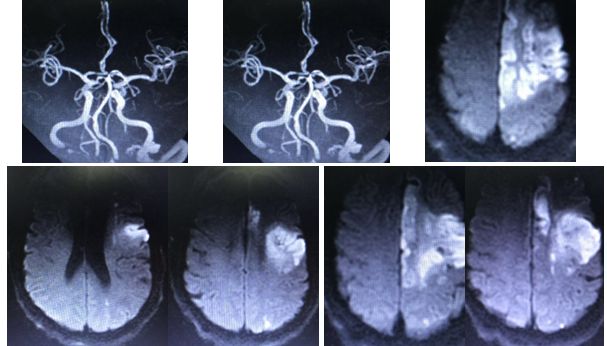

16:00:患者查颅脑磁共振

16:10:左侧额叶、顶叶、侧脑室旁多发急性脑梗死;多发缺血、梗死、软化灶;

左侧颈内动脉闭塞,具体原因不详,狭窄?夹层?

17:20颅脑CT排除出血

入院时颅脑CT(3.19)小脑梗塞

术后复查颅脑CT